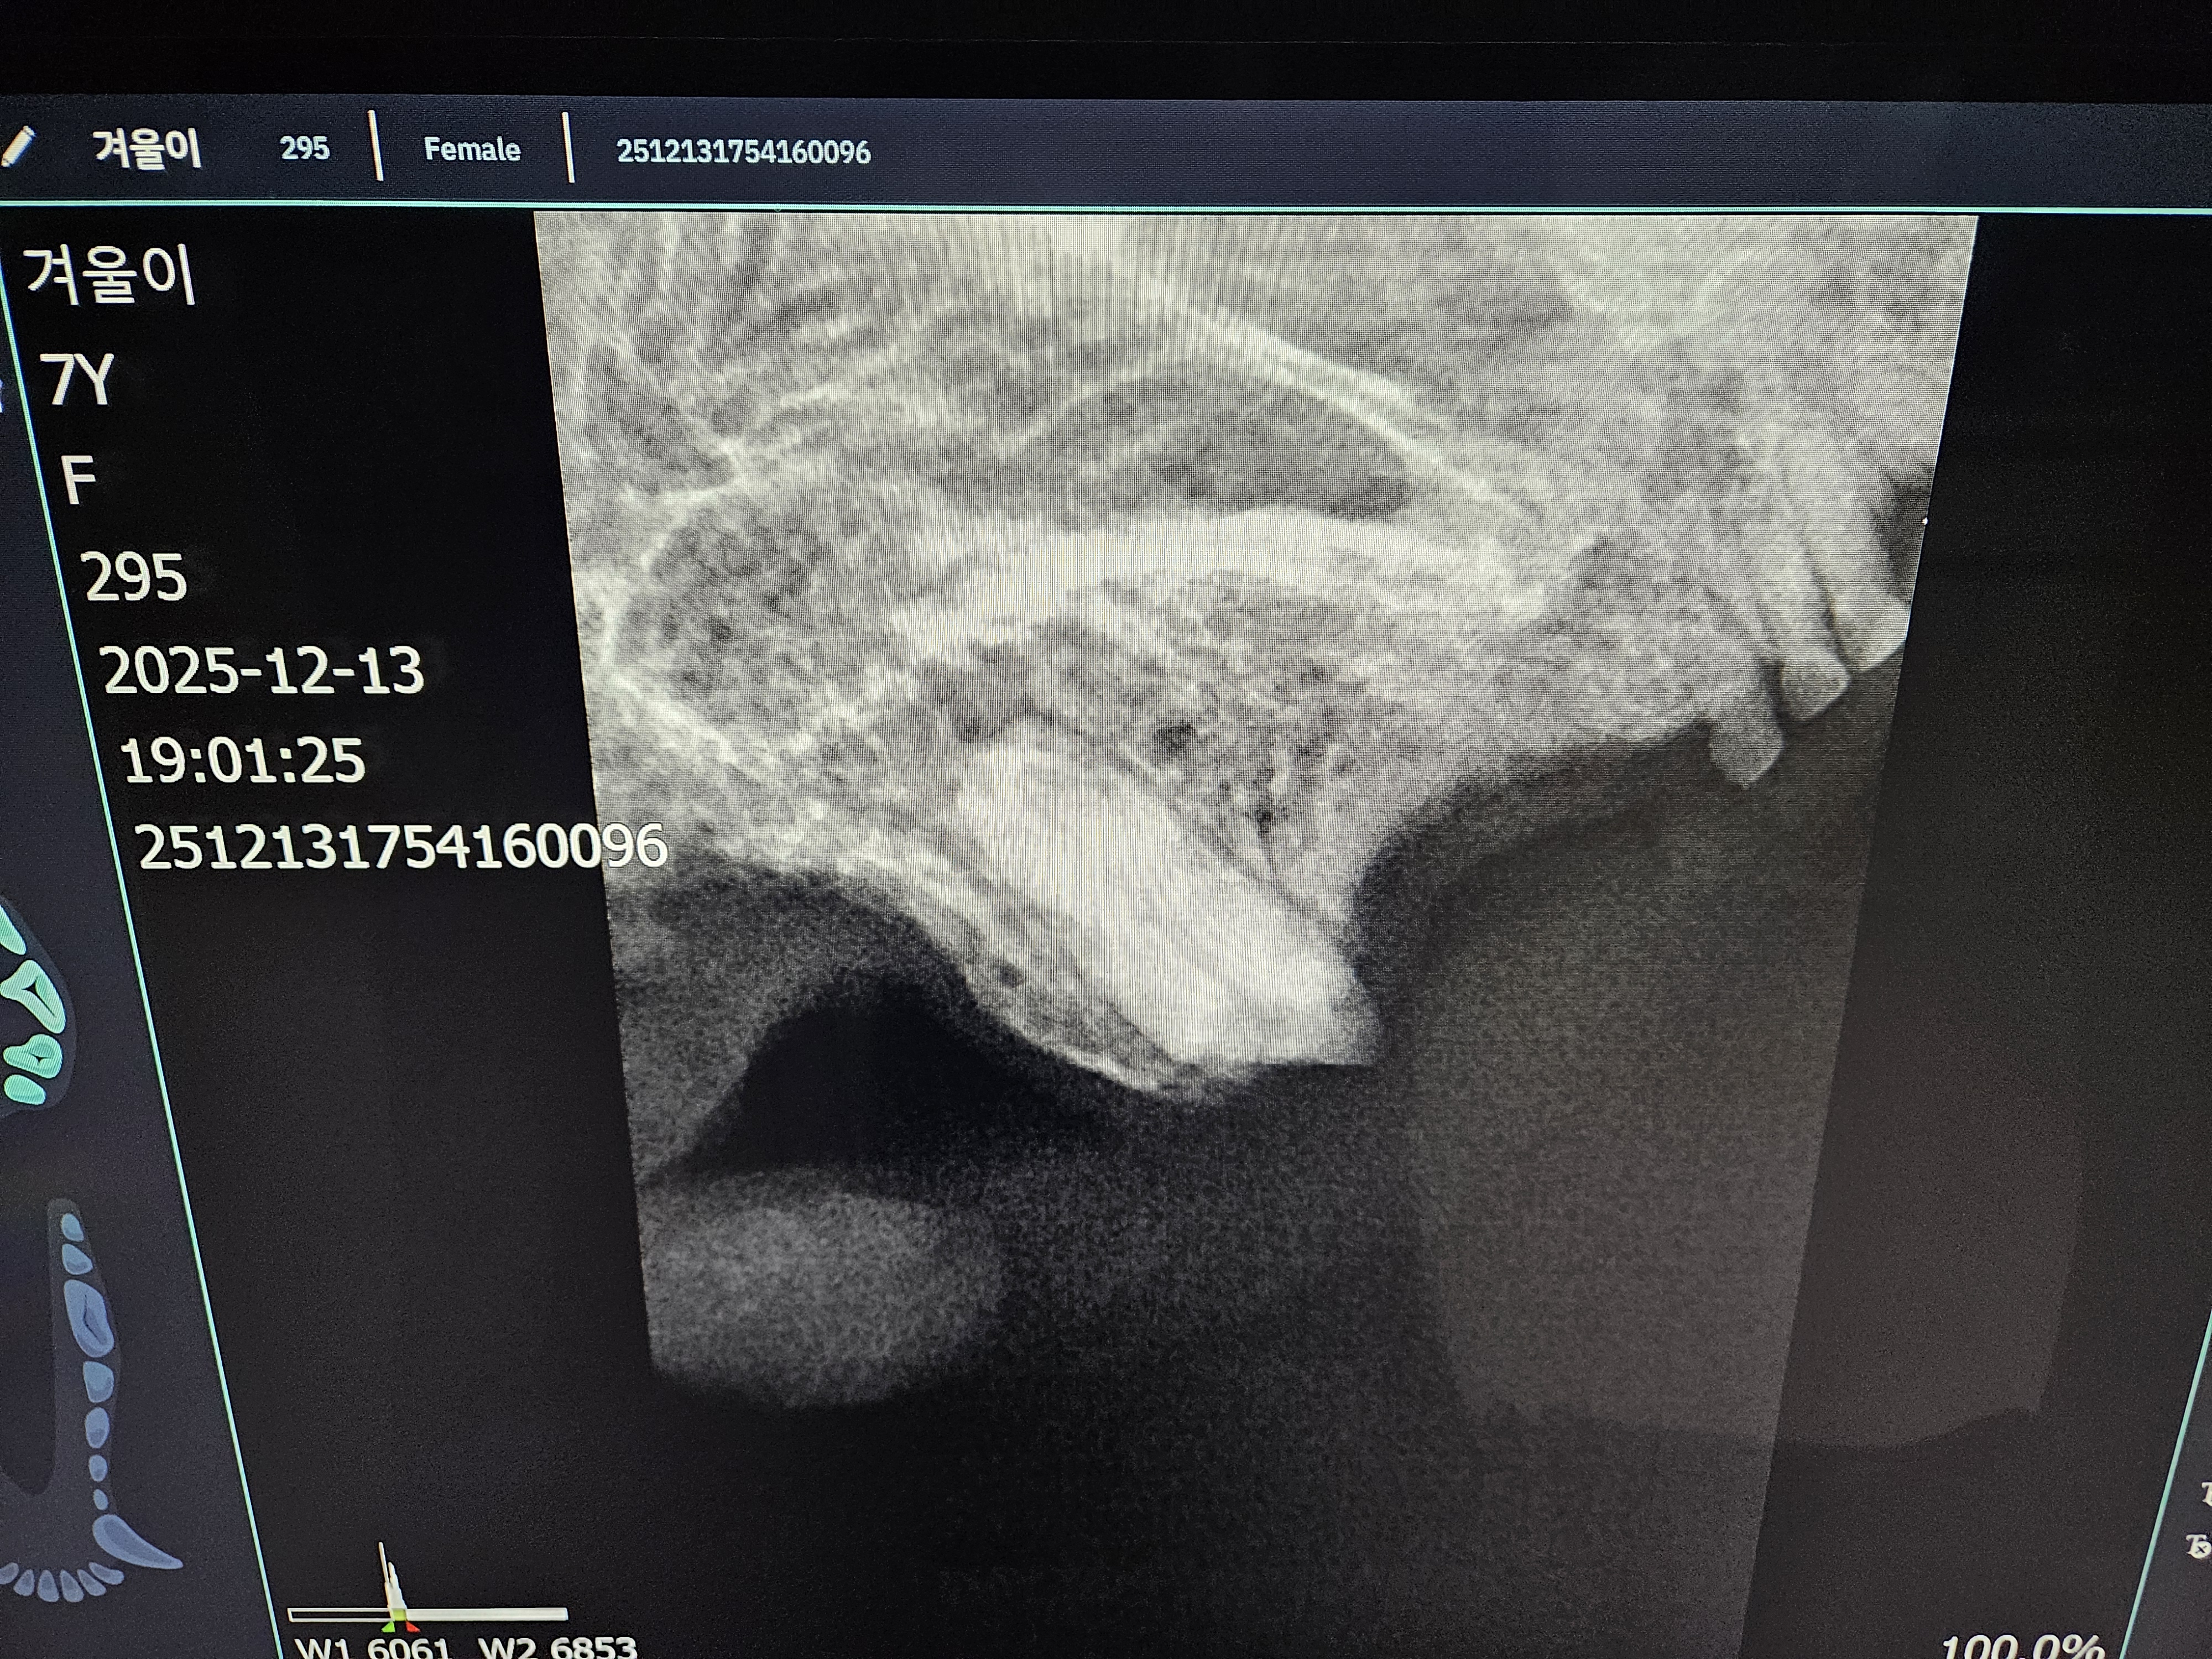

*치아 엑스레이 사진 입니다.

| 치료과정 | 겨울이 염증 수치가 엄청 높았습니다. 보통 정상 수치가 5까지인데 109정도로 엄청 높게 나왔다고 합니다. 염증 수치 같은 경우는 단점이 어떤 부위에 문제가 있는지를 나타내는 수치는 아님. 그런데 겨울이는 구강 안쪽이 엄청 빨개졌었음. 그래서 구내염에 의한 급성염증 수치라고 생각하면 되고, 마취 전에 한 검사는 간수치랑 신장 수치를 체크해주셨는데 콩팥이나 다른 부위는 기능이 정상이라고 하셨습니다. 겨울이 같은 경우는 밥을 잘 못먹었을 뿐이지 간수치나 신장 수치는 특이사항이 없다고 하셨습니다. 겨울이가 입원한 날 빈혈이 너무 심해가지고 수액을 맞았습니다. 그런데 적혈구 개체수도 부족해서 계속 수액을 맞을 수가 없었습니다. 혈액의 적혈구가 부족한혈액이 점점 많아지는 거예요. 항생제 수액으로 마무리 했다고 하셨고,급성 염증 수치는 시간이 지남에 따라서 무조건 좋아진다고 하셨는데, 약은 항생제와 염증 가라앉히는 소염제를 처방해준다고 하셨습니다. 치아 엑스레이 찍은 결과 치조골이라고 해서 이빨에 잡고 있는 뿌리가 어 다 녹아 있었고,그래서 이런 부분들이 이빨의 기능을 상실한 채로 그냥 이가욱씬욱씬한 상태로 있었을거고, 그래서 이빨을 뽑아야 하는 상태라고 하셨습니다. 송곳니는 부러져 있는 부위도 있어서 그런 이빨들은 뿌리 안남기고, 제거를 하셨다고 했습니다. 이빨 자체가 약한 상태이고 전체적으로 발치를 다 한 상태라고 하셨습니다. |